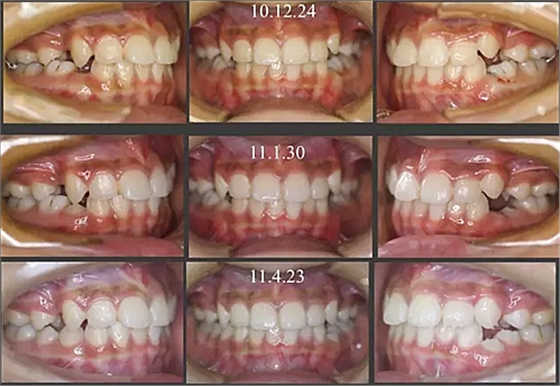

經(jīng)過三年零九個月的看護,最終戴上了固定矯治器,但是大家不難發(fā)現(xiàn),孩子的牙齒已經(jīng)排齊,上下中線也基本對齊,面型也好看多了,這樣矯正就變得簡單,療程自然縮短,孩子也不遭罪了。

這個故事告訴我們,只有家長早點把孩子帶給正畸醫(yī)生檢查,才能早期發(fā)現(xiàn)早期治療。起到了事半功倍的效果。矯正以后還不容易復發(fā),因為從08年的初診到11年戴矯正器這三年多的時間里,孩子的牙齒是自己長好的。